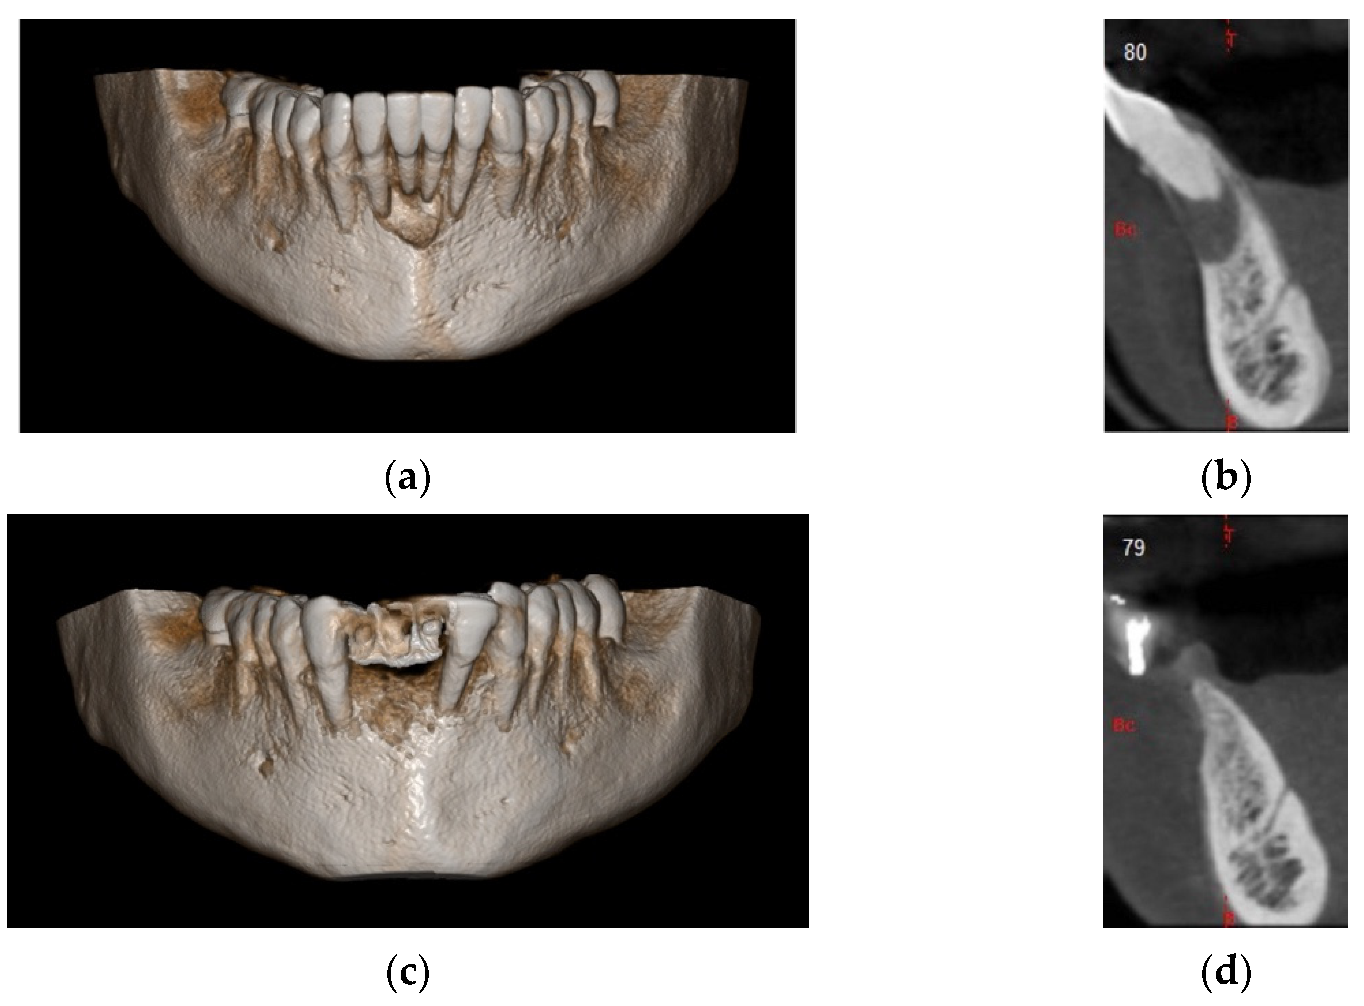

In this case, we observed how modern 3D reconstruction techniques can be a good support in regenerative surgery. In fact, starting from dicom files format, obtained with cone-beam computed tomography (CBCT) (Osteophoenix, Erandio-Vizcaya-Spain) it was possible to simulate “ex-ante” the surgical procedure. In addition to the reconstruction of the mandible (Figure 10a), the extraction of molars 4.6 and 4.7 was also simulated.

Figure 10.

(a) 3D model of the mandible; (b) Titanium foil digital design.

A titanium foil barrier was preventively designed and prepared in order to shorten surgical time (Figure 10b). In fact, the great advantage in cases like this is that the device does not need to be shaped during the surgical session.

4 months after the surgery, the barrier was withdrawn and, behind it, growth of elastic and thick osteoid tissue was observed (Figure 16a,b). After further 4 months, a CBCT was performed, and the amount of regenerated bone was observed (Figure 17a–d).

Figure 16.

(a) Removal of titanium foil after 4 months; (b) osteoid tissue with hard but still elastic consistency covered by not-epithelized mucosa.

Figure 17.

(a) Initial 3D situation; (b) CBCT of the initial situation; (c) Final CBCT post 3D regeneration after 4 months; (d) X-ray of the situation post regeneration after 4 months.

The patient was prosthetically rehabilitated with additional implants positioned in 4.2 and 3.2 (post-extractive). In this case, we also noted how soft tissues surrounding the regenerated site were mature and stable (Figure 18).